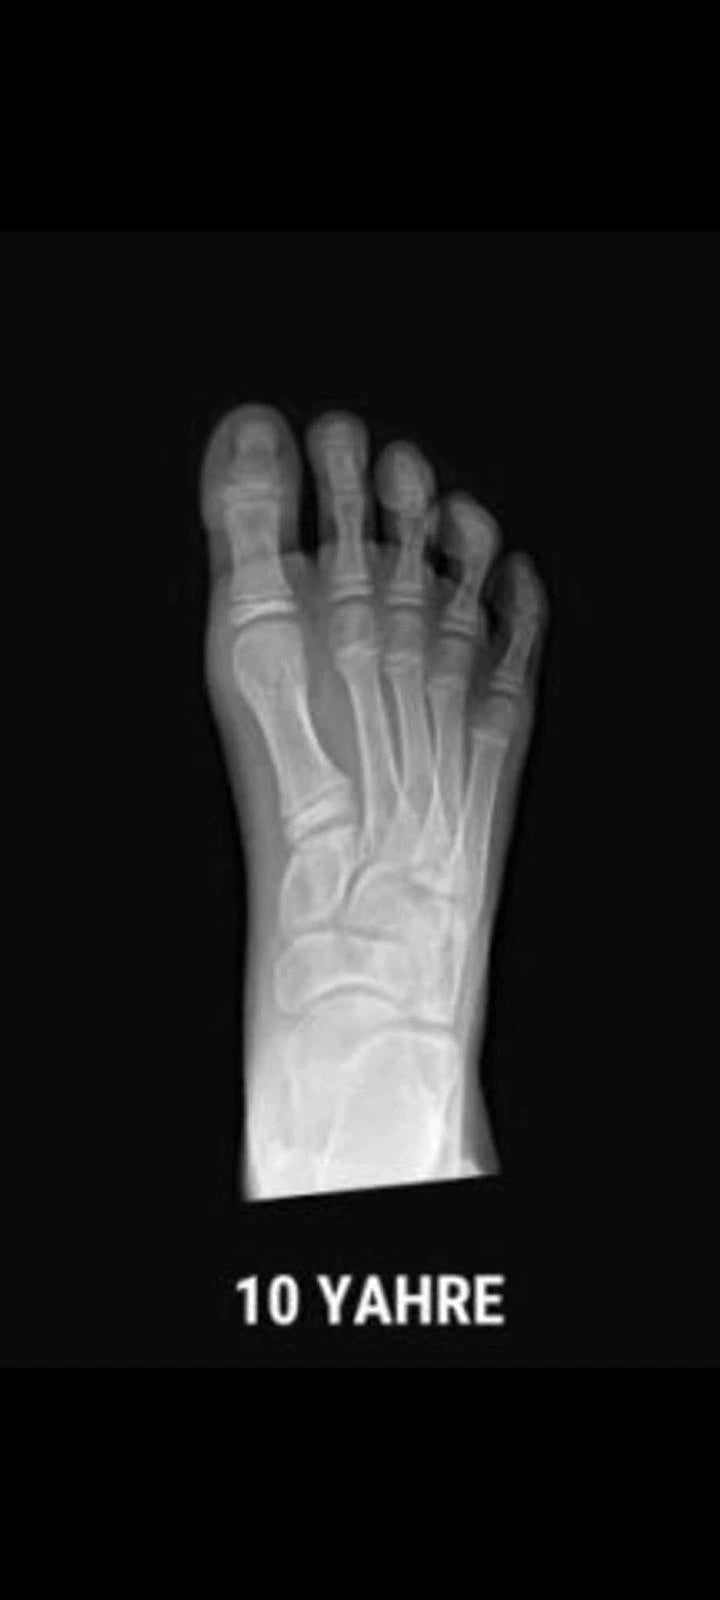

Puntera ancha: pie libre frente a pie comprimido

La horma Gullibare está diseñada para imitar la forma natural del pie de un bebé. Es más ancha en la parte de los dedos para que puedan abrirse y moverse con libertad.

Esto es esencial para un desarrollo saludable del equilibrio, la estabilidad y una distribución uniforme del peso.